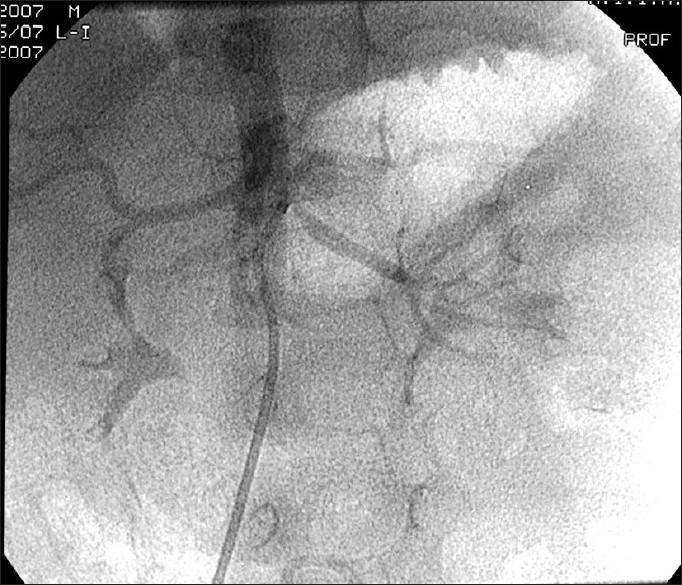

Renal artery stenosis due to neurofibromatosis.

A 4-year-old boy with hypertension due to renal artery stenosis and neurofibromatosis type 1 is presented for its rarity. Renal artery stenosis due to neurofibromatosis is underrecognized and may masquerade Takayasu's arteritis in Asian children.